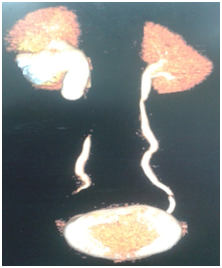

5 year old boy came to our outpatient department with intermittent flank pain since one week. There were no other systemic complaints. Patient was previously investigated & operated for right non palpable testis a year ago. An incidental finding of right mild hydronephrosis (AP Diameter of 12mm) were noted during sonological evaluation. General and systemic examination were normal. Haematological workup was normal. Ultrasonography showed hydronephrosis with antero-posterior diameter of 3.5cm associated with dilatation of upper ureter (dia-9.2 mm). Micturating cystourethrogram was done to rule out vesico ureteric reflux. DTPA renal scan was suggestive of preserved parenchymal function & GFR with significant subrenal obstruction at right peviureteric junction along with upper hydroureter. CT-IVP demonstrated right hydronephrosis with dilatation of the upper ureter due to kinking at junction of upper & middle ureter suggestive of obstruction (Figures 1&2). Left kidney was normal.

Figure 2 3D reconstructed image.